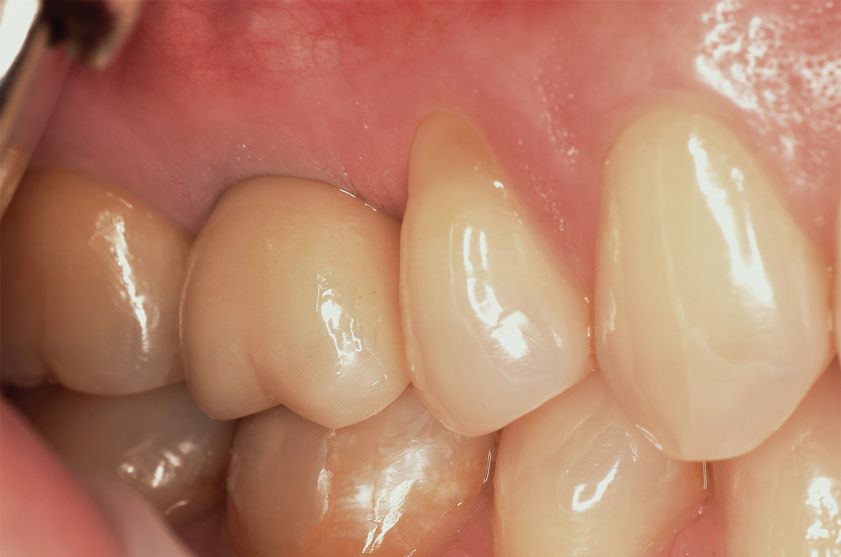

(13.) Radiograph immediately following implant placement with cover screw on the implant.

Figure 13

(14.) Radiograph at 36 months posttreatment, demonstrating maintenance of crestal bone level and height of the augmented sinus.

Figure 14